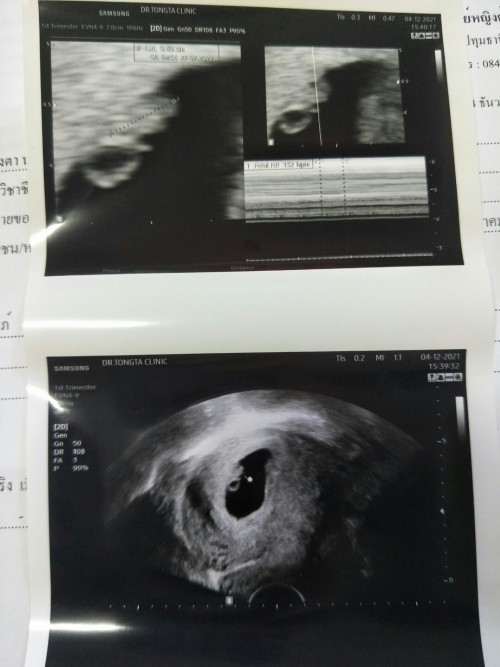

กี่ weeks ถึงจะตรวจเจอการเต้นของหัวใจลูกน้อยคะ

ตอนนี้น้อง 6 weeks 2 days